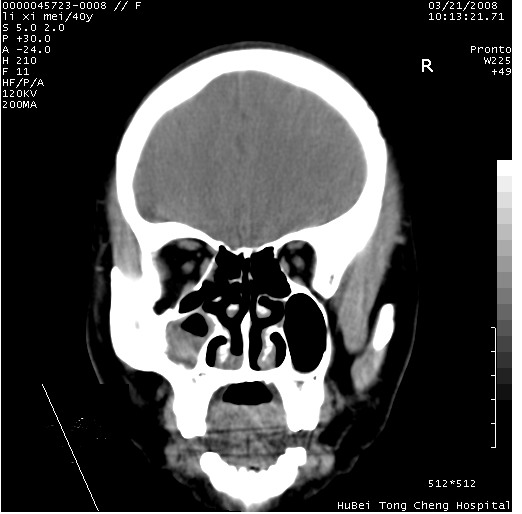

以下是引用卜一在2008-3-21 20:18:00的发言:[br]双侧上颌窦炎症,双下鼻甲肥大!不除外霉菌感染!

以下是引用qiuleiyu在2008-3-21 21:46:00的发言:[br]支持;上颌窦炎,窦内高密度影,建议横断位观察与上颌窦前壁关系。除外骨源性病变。